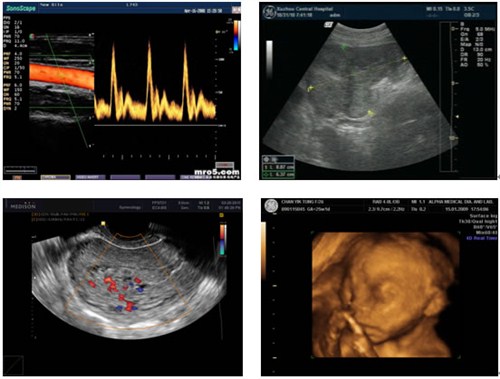

菲力姆数码科技有限公司 菲力姆科技有限公 菲力姆科技有限公司成立于2013年,注册资本1000万,公司总部位于大湖名城创新高地合肥市,是一家专注于医用胶片研发、生产、销售的高新技术企业,主营产品有高清B超胶片、干式热敏胶片及医学影像整体输出打印解决方案、医用一站式自助取片机等。 公司成立至今已获得医疗器械生产许可证、医疗胶片注册证、打印机注册证、软件著作证书等行业准入证书,通过了ISO9001质量体系认证、3C认证、CE认证等权威机构认证,并获得了数十项行业内发明专利。形成了近百人的生产、销售、售后团队,其中国内前列高分子材料研发工程师、软硬件工程师、技工数十人,销售、售后网络遍布全国。